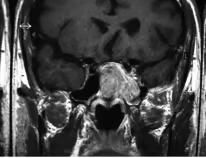

PubMedVision 是一个用于医学多模态能力评估的数据集,涵盖多种医学成像模态与解剖区域,旨在为多模态大语言模型(MLLMs)在医疗视觉-文本理解任务方面提供标准化测试资源,以检验它们在医学领域的视觉知识融合与推理性能。